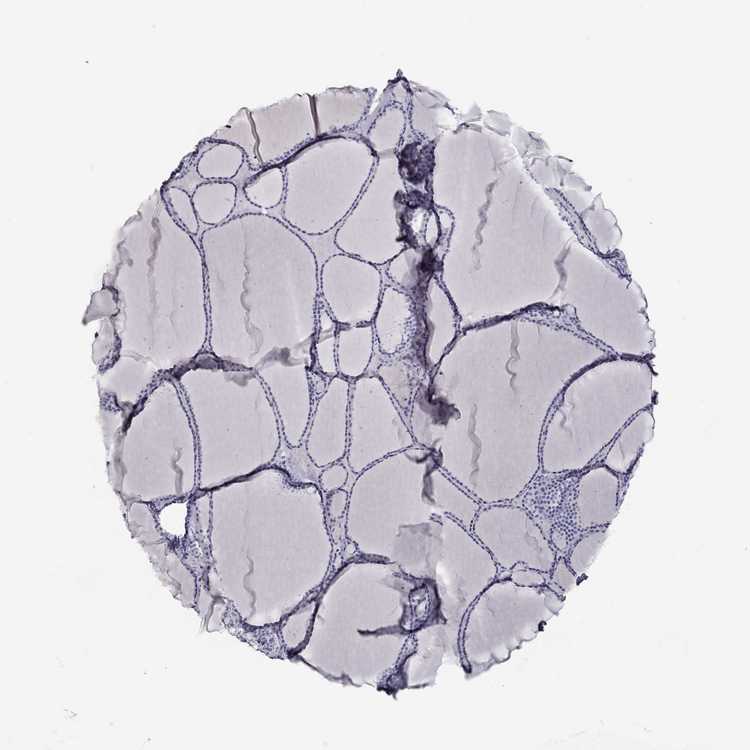

TISSUE PRIMARY DATA THYROID GLAND Show tissue menu

THYROID GLAND - Antibody stainingi

Antibody staining in the annotated cell types in the current human tissue is reported as not detected, low, medium, or high, based on conventional immunohistochemistry profiling in selected tissues. This score is based on the combination of the staining intensity and fraction of stained cells.

Each image is clickable and will lead to virtual microscopy that enables deeper exploration of all samples and also displays staining intensity scores, fraction scores and subcellular localization as well as patient and tissue information for each sample.

Antibody HPA046135Antibody HPA063644Antibody CAB002762Antibody CAB079881

Glandular cells Not detectedNot detectedNot detectedNot detected